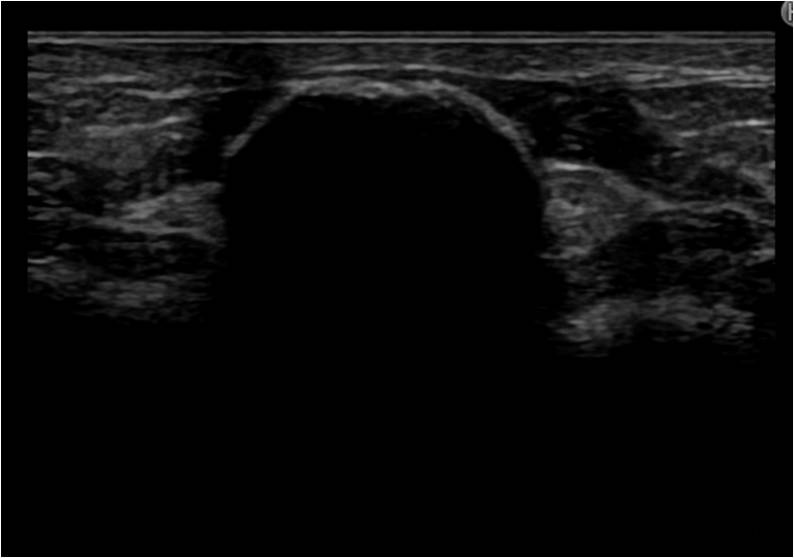

上のしこりは、石灰化パターンのしこりです。しこりはパターンによって治療方針が異なります。

この状態ですと、乳がん検診なども受けることもできません。

この方は、乳輪切開し、摘出となりました。